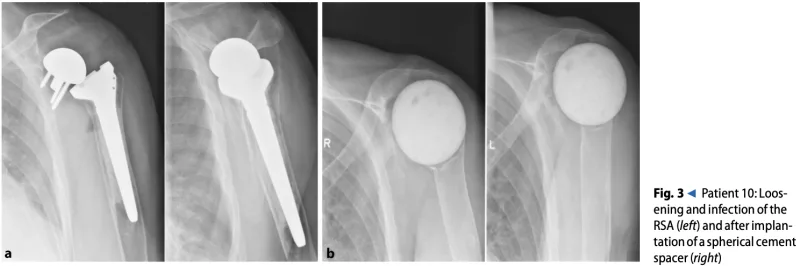

この方は1年前に当科でリバース型人工肩関節置換術を受けられていました.

2カ月前から肩甲骨に入れた人工肩関節の部品がゆるんできたため, 人工関節を抜き取る手術が行われました.

手術中の所見では, 肩甲骨の部品の周りに膿が貯まっていたため, 細菌感染は完全には沈静化してなかったようでした. 術後の経過は良好でしたが, 朝は嘔気のため朝食を摂れなかったとのことでした.

朝に嘔気を訴えていた人工肩関節抜去後の患者さんは, 昼食を摂れるまでに回復し, 自力歩行も再開されていました.